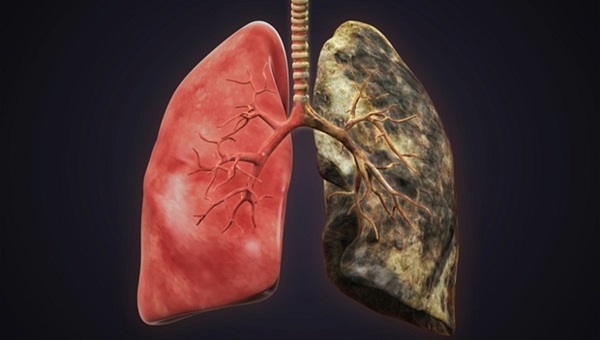

Οι πνεύμονες ενός καπνιστή

Οι υγιείς πνεύμονες έχουν ανοικτό ροζ χρώμα, ενώ οι πνεύμονες ενός καπνιστή έχουν σκούρο χρώμα και στίγματα οφείλονται στην εισπνεόμενη πίσσα από το τσιγάρο. Η υφή των δύο διαφέρει επίσης, με τον κατεστραμμένο πνεύμονα να είναι πολύ πιο σκληρός και “εύθραυστος” σε σχέση με τον υγιή.